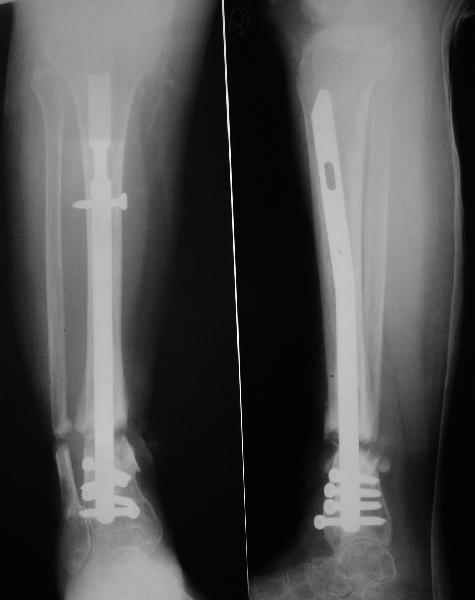

Аппарат - чтобы плавно исправить ось. В приложении - снимки на момент окончания коррекции в аппарате, фото с операции, и послеоперационная рентгенограмма.

Диаметр гвоздика 10,5 мм. Пришлось укорачивать до 23 см - уж очень миниатюрная дама, отверстия насверлил под 45 градусов, под 5 мм винты. По оси удалось сблизить до этого положения. Заперли гвоздь пока статически с планом через 2 месяца верхний винт убрать. Но это ей придется уже в Ташкенте сделать. Что скажете? Спасибо.

In attachment - x-rays at the end of alignment, the surgery, and result. The nail was cut to 23 cm. Four 45 degree holes were pre-drilled at the distal nail tip. The nail was locked statically

after some impaction. Dynamization is considered in 8 weeks. Any comments/critics?

Отправитель: Nuno Craveiro Lopes 27 Апрель 2005, 02:10

Alex,

> In attachment - x-rays at the end of alignment, the surgery, and

> result. The nail was cut to 23 cm. Four 45 degree holes were

> pre-drilled at the distal nail tip. The nail was locked statically

> after some impaction.

Amazing! How can you find the pathway of the nail through all those wires and the distal screws through so much hardware?